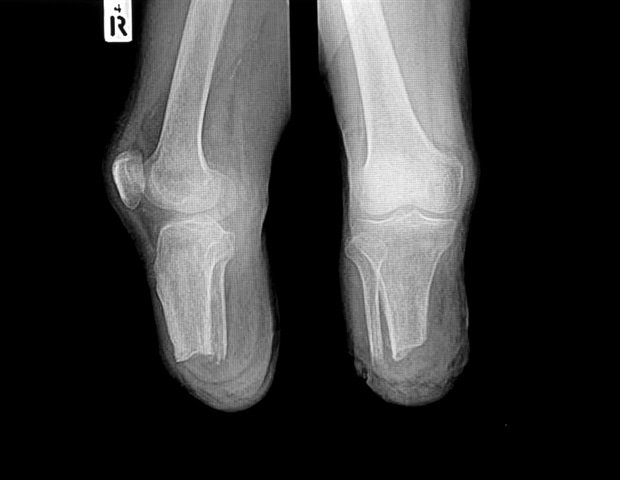

HSS researchers set out to examine initial results of osseointegration with custom-made 3D printed implants required to achieve the ideal fit for a specific patient.

“Some designs of press-fit osseointegration implants have standard curvatures and contours with patient-specific lengths, which can sometimes be difficult to match to the shape of the remaining bone,” Dr. Hoellwarth explained.

Dr. Leaf, who presented the research at the AAOS conference, said additive manufacturing using electron beam melting (EBM) allows for the production of precision osseointegration implants that provide an optimal fit, making it possible to reconstruct nearly any remaining bone segment to meet an individual’s anatomical needs.

HSS researchers retrospectively reviewed the records of 19 HSS patients who underwent osseointegration with custom 3D printed implants planned from preoperative CT scans. Patients included patients who underwent above-knee, below-knee, and above-elbow osseointegration surgery between May 2024 and March 2025.